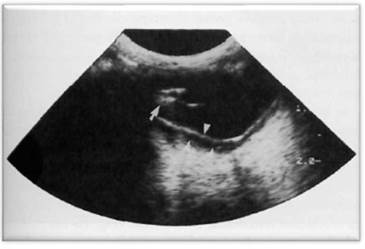

Cuando se habla de ecografía ocular es importante realizar comparación del ojo contra lateral, siempre que sea posible, diferenciando las distintas estructuras oculares como lo son: cornea, cámara anterior, lente (cristalino), cuerpo ciliar, cámara posterior, cámara vítrea, retina y nervio óptico (Figura 9) 10. Además de realizar diferentes cortes: longitudinales, transversales y axiales que permitan diferenciar posibles anormalidades, su ubicación y medida.

Comparando con el caso clínico, y de acuerdo a lo reportado en la bibliografía se puede observar que el ojo izquierdo está ecográficamente normal (Figuras 10 y 11), ya que se identifican todas las estructuras anatómicas normales, sin ningún tipo de alteración.